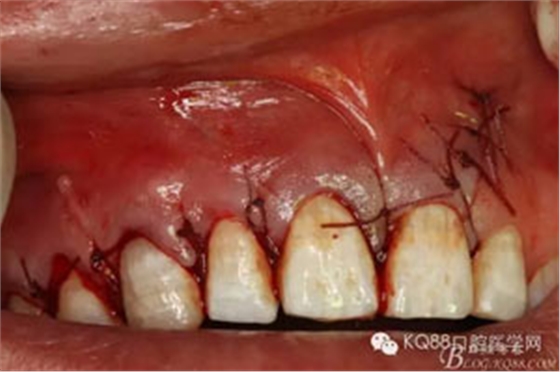

圖3.局部麻醉下,行唇側(cè)21垂直切口+齦溝內(nèi)水平切口

圖4.翻瓣、去除覆蓋在囊腫表面骨質(zhì),暴露出囊壁。

圖12.縫合創(chuàng)口